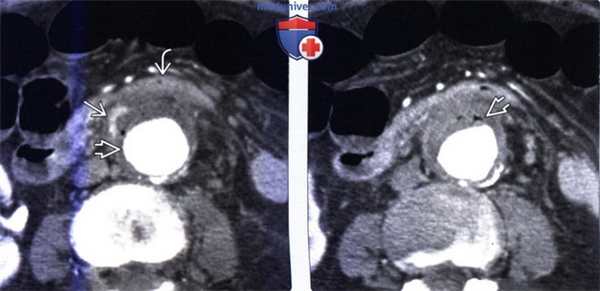

(Слева) На аксиальной КТ с контрастированием у женщины с жалобами на боль и лихорадку, возникшими спустя несколько лет после вмешательства по поводу аневризмы брюшного сегмента аорты, визуализируется обызвествленная стенка аорты, обернутая вокруг синтетического стента. На уровне третьей части двенадцатиперстной кишки ее стенка спаяна с аортой. Обратите внимание на гиперденсный участок, появляющийся при контрастировании, представляющий собой активное кровотечение или воспаление.

(Справа) На аксиальной КТ у этой же пациентки визуализируются несколько пузырьков внепросветного газа, во время операции была подтверждена аорто-энтеральная фистула и инфекционный процесс как причина ее возникновения.